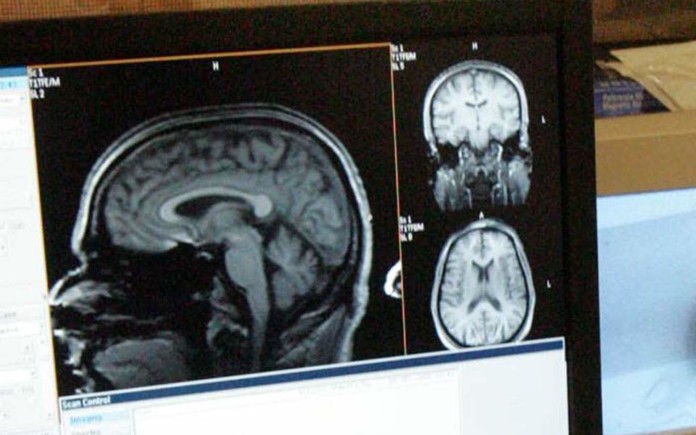

Η πρώτη, με επικεφαλής τον καθηγητή ακτινολογίας Χρήστο Νταβατζίκο της Ιατρικής Σχολής του Πανεπιστημίου της Πενσιλβάνια, αφορούσε 307 ασθενείς έως 45 ετών με σχιζοφρένεια και 364 υγιείς (ομάδα ελέγχου) σε τρεις χώρες (ΗΠΑ, Γερμανία, Κίνα). Παρουσιάστηκε στο περιοδικό νευροεπιστήμης “Brain” (Εγκέφαλος) και ανακάλυψε για πρώτη φορά ότι υπάρχουν δύο διαφορετικοί τύποι σχιζοφρένειας, διακριτοί μεταξύ τους από άποψη νευροανατομίας.

Η πρώτη έρευνα είναι η πρώτη που ανακαλύπτει διεθνώς ότι ο ένας τύπος σχιζοφρένειας, που είναι ο πιο συχνός, εμφανίζει μικρότερο όγκο φαιάς ουσίας στον εγκέφαλο σε σχέση με τους υγιείς ανθρώπους, ενώ ο δεύτερος τύπος (σχεδόν το 40% των ασθενών) έχει όγκο παρόμοιο με τον εγκέφαλο των υγιών. Η ανάλυση των απεικονιστικών εξετάσεων του εγκεφάλου όλων των ατόμων έγινε με τη βοήθεια του συστήματος τεχνητής νοημοσύνης “HYDRA”, που ανέπτυξε η ομάδα του ελληνικής καταγωγής ακτινολόγου.

«Πολλές άλλες μελέτες έχουν δείξει στο παρελθόν ότι οι άνθρωποι με σχιζοφρένεια έχουν σημαντικά μικρότερους όγκους εγκεφαλικού ιστού σε σχέση με τους υγιείς. Όμως τουλάχιστον στο ένα τρίτο των ασθενών», δήλωσε ο δρ Νταβατζίκος (απόφοιτος της Σχολής Ηλεκτρολόγων Μηχανικών του ΕΜΠ το 1989, ειδικός σε θέματα βιοϊατρικής απεικόνισης και ανάλυσης), «βρήκαμε ότι αυτό δεν συμβαίνει, καθώς ο εγκέφαλος τους είναι σχεδόν τελείως φυσιολογικός. Στο μέλλον δεν θα συνεχίσουμε να λέμε ότι ‘ο ασθενής έχει σχιζοφρένεια’. Θα λέμε ότι ‘έχει αυτό τον υποτύπο σχιζοφρένειας’ ή ‘αυτό το μη φυσιολογικό πρότυπο’, αντί να έχουμε μια μεγάλη ομπρέλα κάτω από την οποία θα κατηγοριοποιούμε τους πάντες».